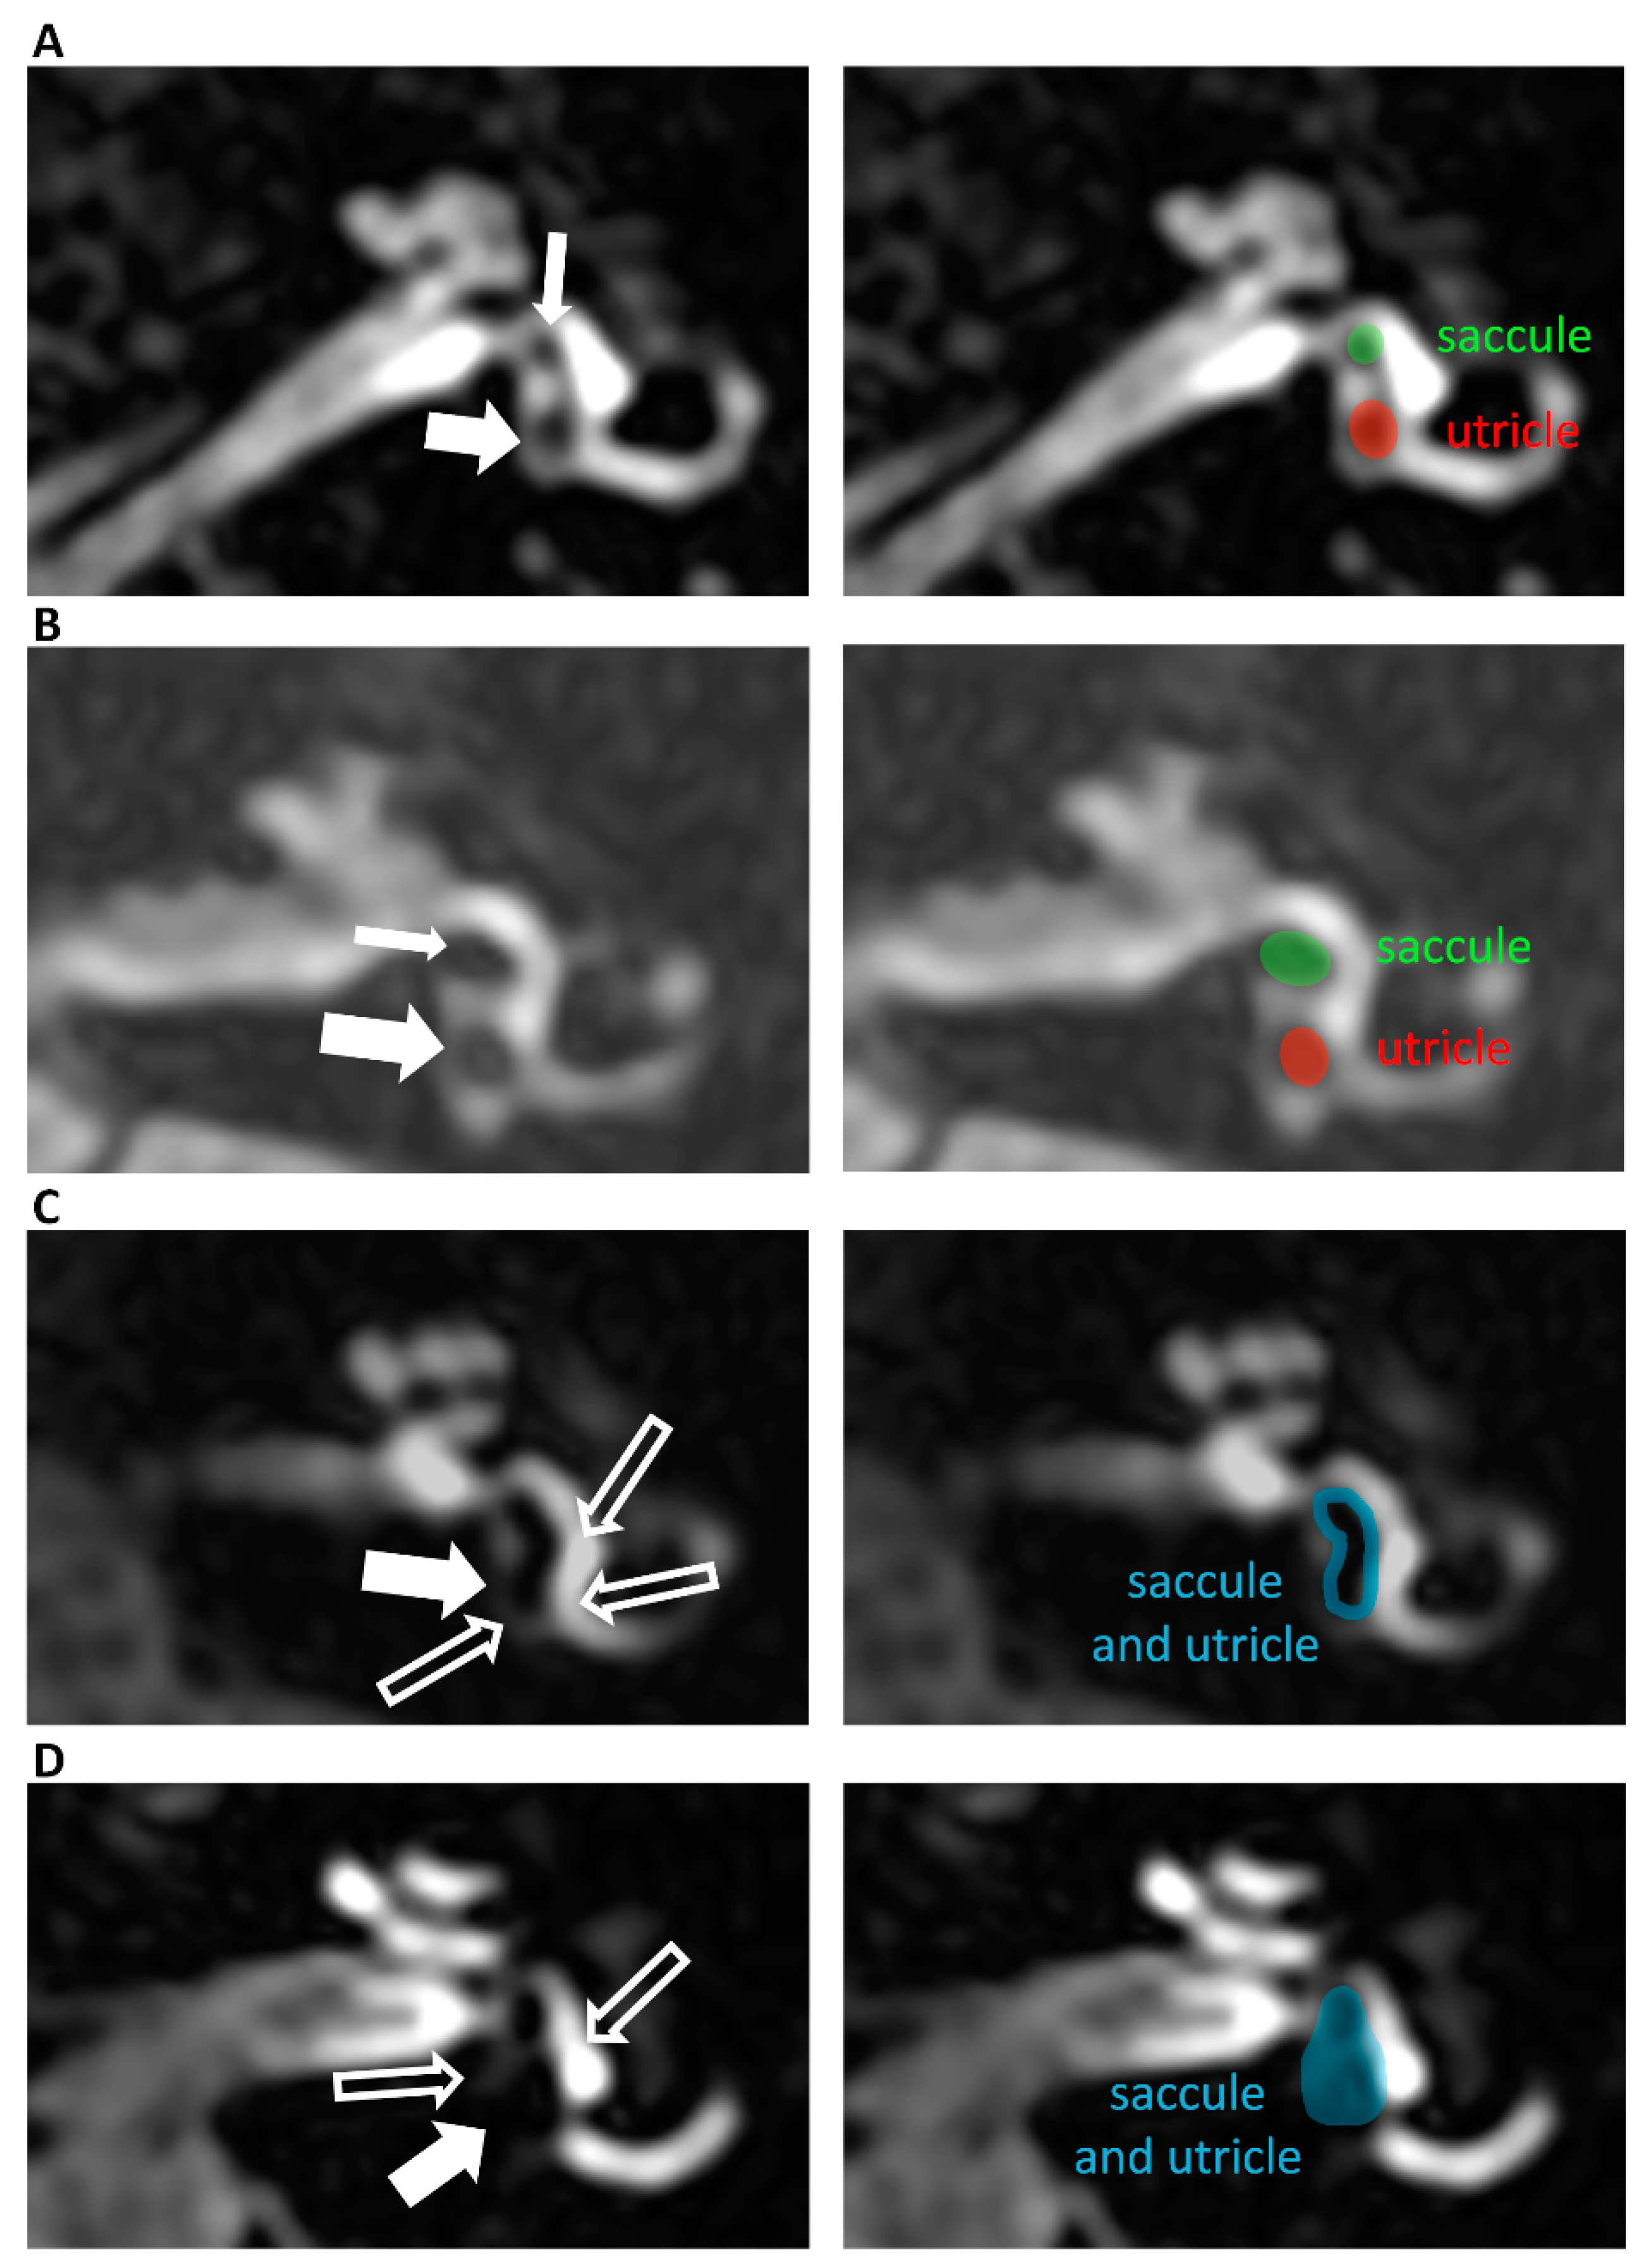

- Attye, A.; Eliezer, M.; Boudiaf, N.; Tropres, I.; Chechin, D.; Schmerber, S.; Dumas, G.; Krainik, A. MRI of endolymphatic hydrops in patients with Meniere’s disease: A case-controlled study with a simplified classification based on saccular morphology. Eur. Radiol. 2017, 27, 3138–3146. [Google Scholar] [CrossRef]

- Bernaerts, A.; Vanspauwen, R.; Blaivie, C.; van Dinther, J.; Zarowski, A.; Wuyts, F.L.; Vanden Bossche, S.; Offeciers, E.; Casselman, J.W.; De Foer, B. The value of four stage vestibular hydrops grading and asymmetric perilymphatic enhancement in the diagnosis of Meniere’s disease on MRI. Neuroradiology 2019, 61, 421–429. [Google Scholar] [CrossRef]